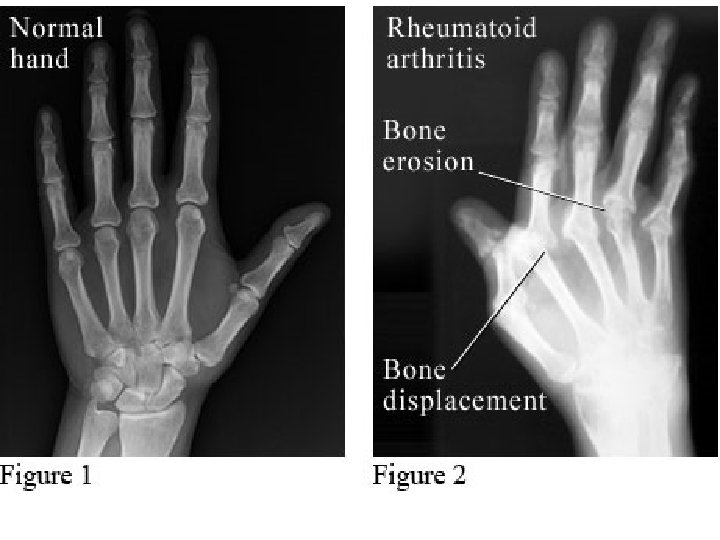

4. Radiology: • Evaluate disease activity & joint damage. a. Plain Films. b. Color Doppler U/S & MRI

Severe case • >20 persistently inflamed joints • Rapid decline in functional capacity • Radiographic evidence of rapid progression of bony erosions & loss of cartilage • Extra-articular manifestations.